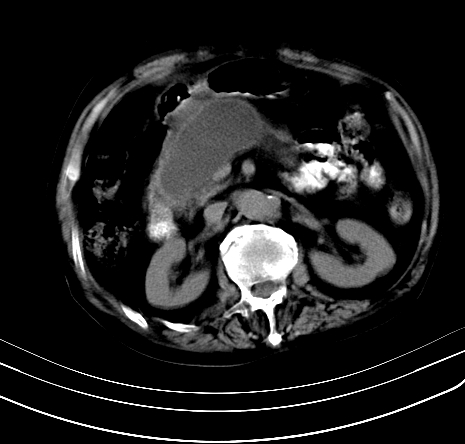

上腹部疼痛不适,行ct检查

胰腺明显肿大,密度减低,考虑慢性胰腺炎,假性囊肿形成不除外。

胰腺明显肿大,密度减低,考虑慢性胰腺炎,假性囊肿形成不除外!支持!

胰腺较明显扩大,胰周有渗出;肾周筋膜有增厚渗出,以左肾为著。应考虑急性胰腺炎。